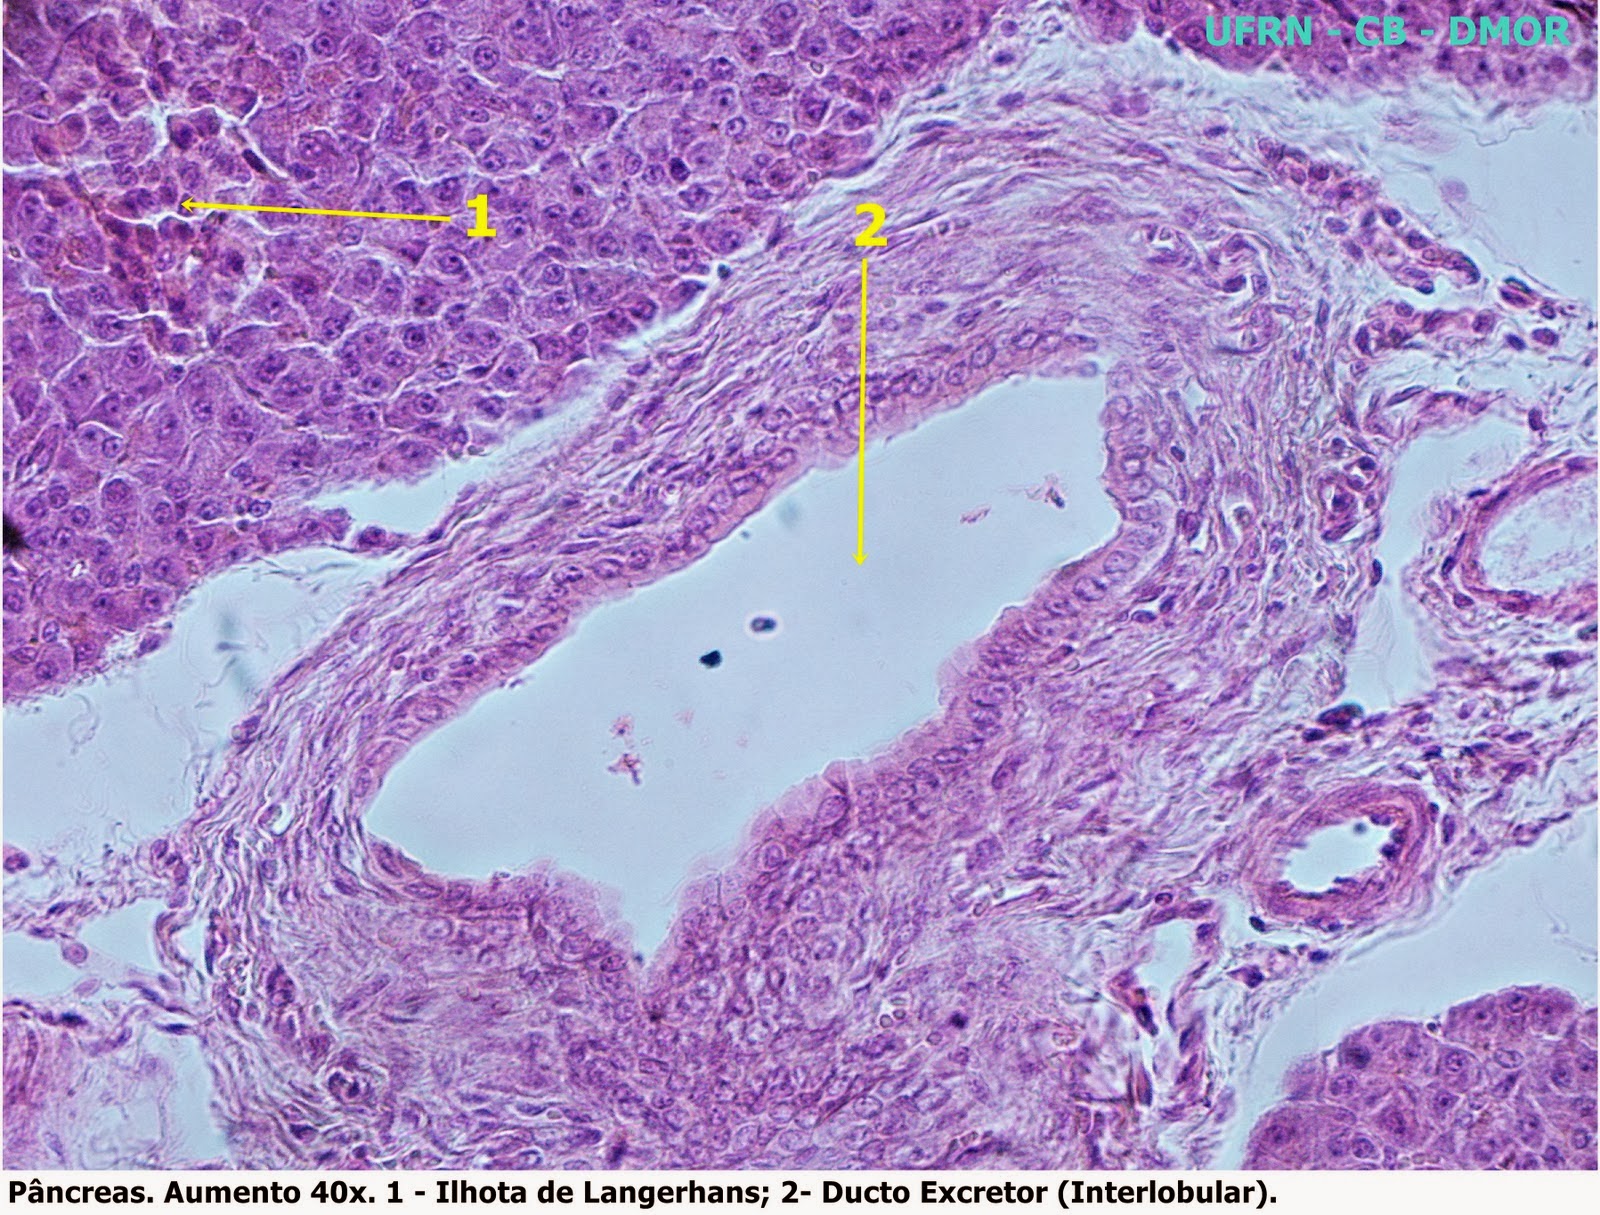

Pâncreas

- O pâncreas é uma glândula mista, de mais ou menos 15 cm de comprimento e de formato triangular, localizada transversalmente sobre a parede posterior do abdome, na alça formada pelo duodeno, sob o estômago.

- O Pâncreas é uma glândula composta acinosa, exclusivamente serosa. Nota-se também a ausência de ducto estriado, contando com a presença apenas dos ductos intercalar e excretor. O Ducto intercalar adentra os ácinos, podendo ser notada células mais claras dentro destes.

- O pâncreas exócrino produz enzimas digestivas, em estruturas reunidas denominadas ácinos. Os ácinos pancreáticos estão ligados através de finos condutos, por onde sua secreção é levada até um condutor maior, que desemboca no duodeno, durante a digestão.

- O pâncreas endócrino secreta os hormônios insulina e glucagon. Ele se encontra dentro da parte exócrina, formando ilhotas.